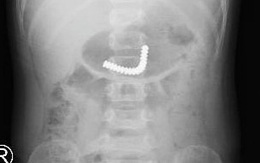

Bé trai 3 tuổi ở quận 8 nuốt 18 bi nam châm trong máy massage  của mẹ

TTO - Trong lúc cầm chơi, bé trai 3 tuổi nuốt 18 viên bi nam châm trong máy massage mắt vào bụng. Dị vật xuống ruột non, dính kết chùm. Các bác sĩ phải đưa đoạn ruột non chứa dị vật ra vết mổ chỗ rốn và mở hỗng tràng để lấy dị vật.